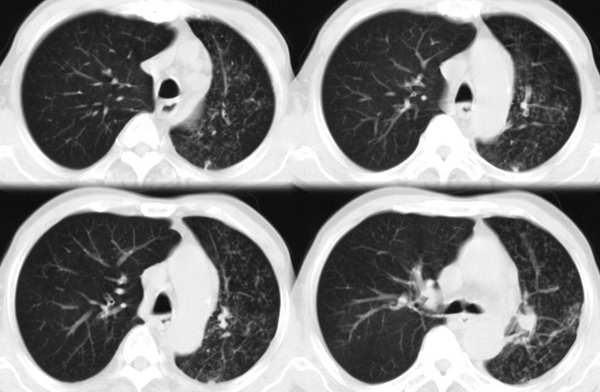

m67y外院ct诊断肺ca,现来我科复查ct

左肺下叶支气管狭窄局部见肿块影左肺下叶不张,肺癌应该没问题吧

典型中央型肺ca

左主支气管变窄,左下叶部分不张,考虑肺癌可能性大

考虑左下肺中央型肺癌并肺不张,建议支气管镜检查。

左下肺中央型肺癌并不张可能性大,为慎重起见,请楼主提供病史,以排除支气管内膜结核引起肺不张。

主-肺动脉窗似有大的淋巴结,肝也像有多发低密度灶。看不太清,是不是转移?

左中央型肺癌并左下叶肺不张,建议纤支镜检查.

左下肺中央肺ca并下肺不张